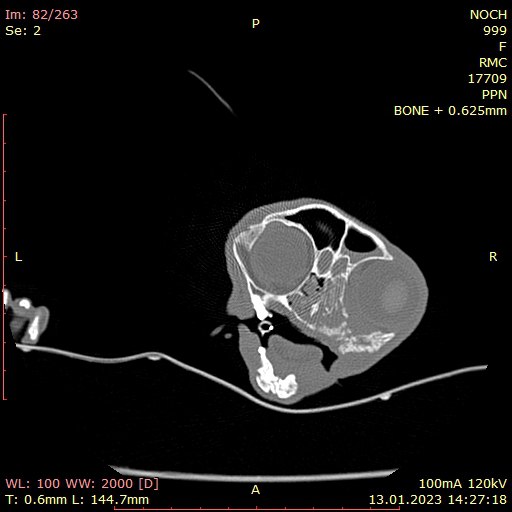

КОМП'ЮТЕРНА ТОМОГРАФІЯ - метод, заснований на отриманні пошарового рентгенівського зображення.

Тому, ми отримуємо можливість точно встановити локалізацію та поширеність патологічного процесу, а також оцінити результат лікування.